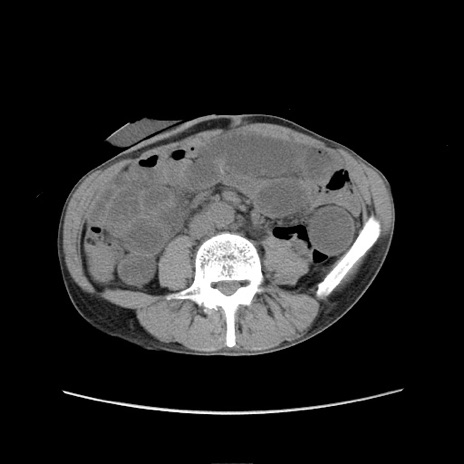

症例11(横断像)

【症例】 60歳代男性

【主訴】 下腹部痛

【現病歴】 本日夜中より下腹部痛の症状認め、受診。

【既往歴】 膀胱癌(膀胱全摘+尿管皮膚瘻術) 、胃癌術後

【身体所見】 BT 35.3℃、PR 58/min、BP 136/98mHg、腹部平坦、軟、腸蠕動音±、ストマ留置あり、左上腹部~正中部に圧痛あり、反跳痛なし。

【データ】WBC 5100、CRP0.01